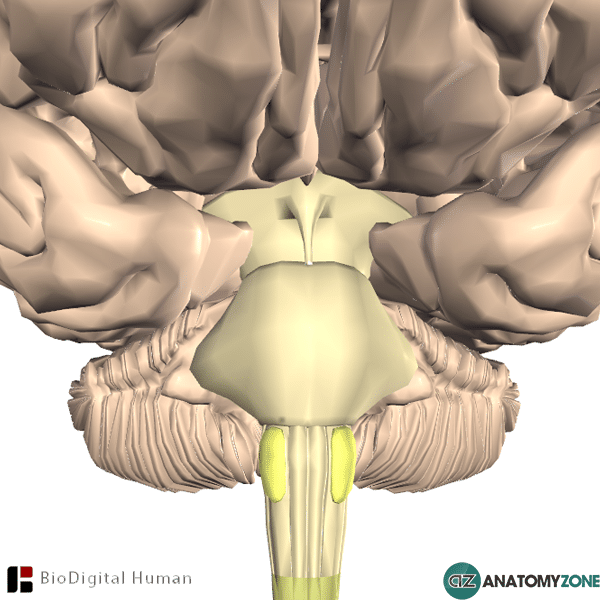

Olives of Medulla - AnatomyZone